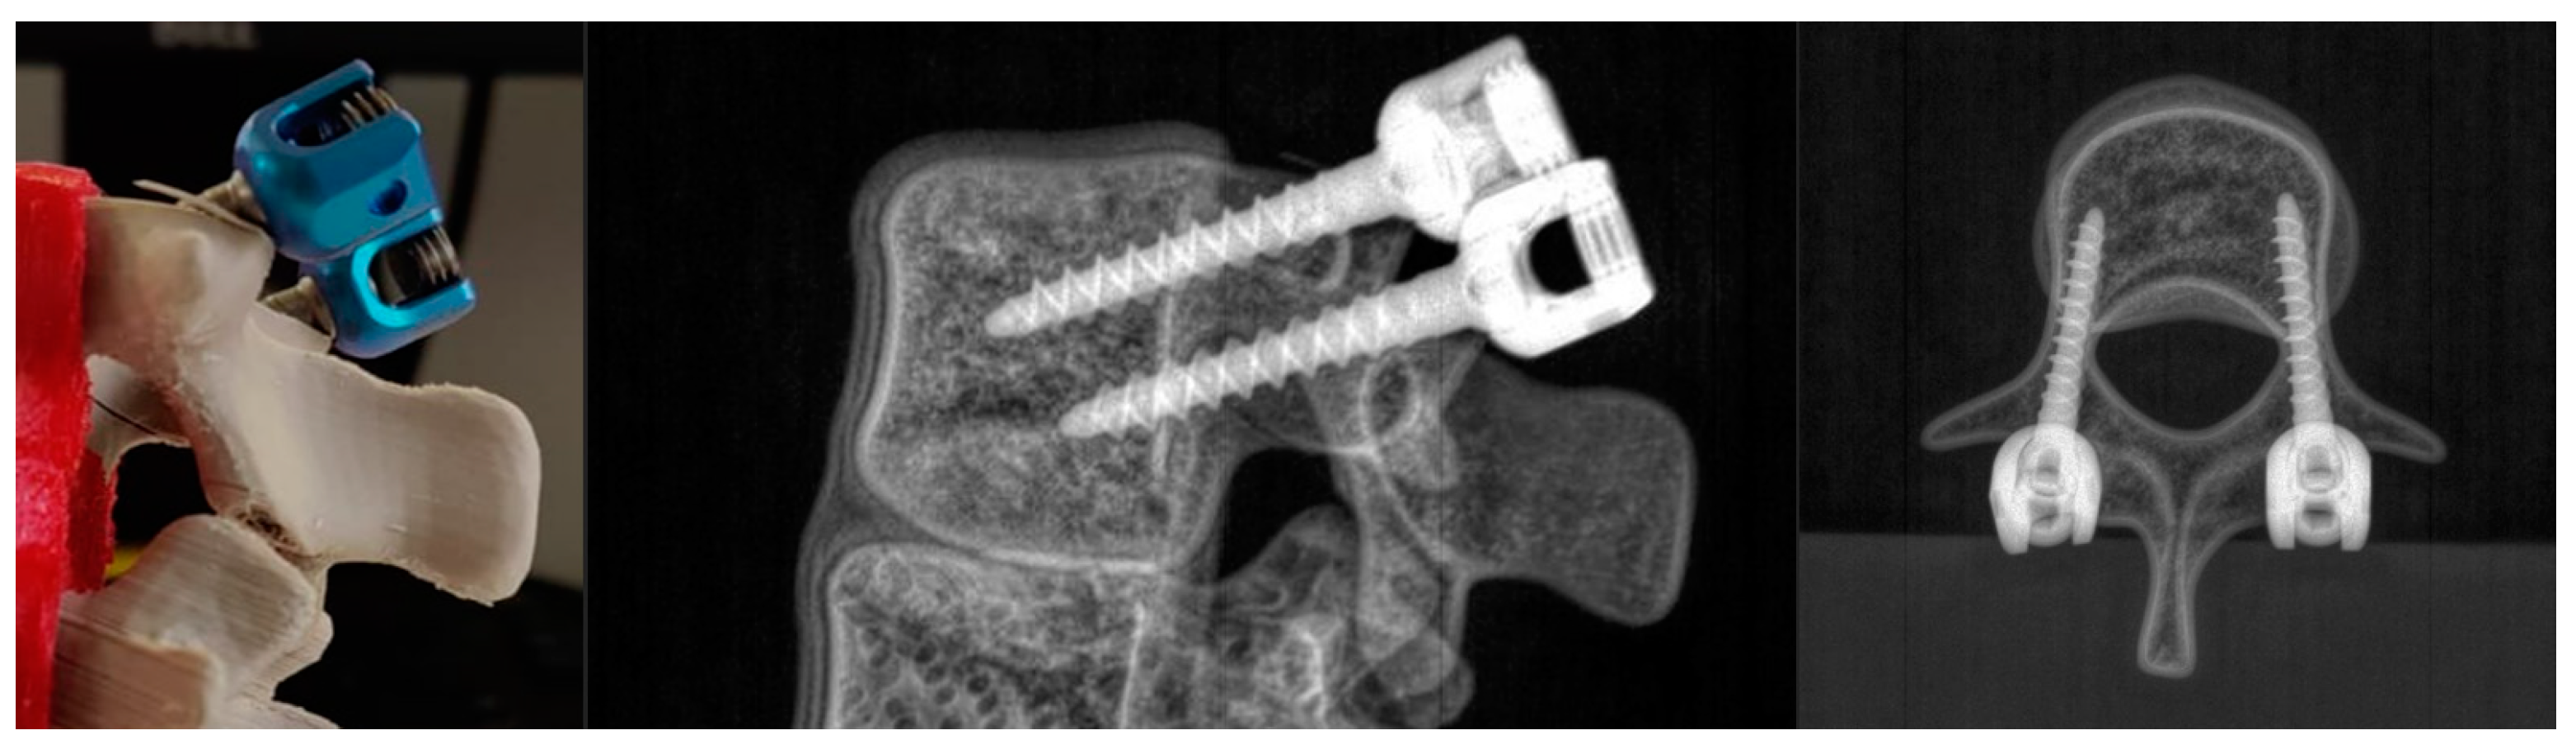

Adequacy of the mechanical behavior of the 3D-printed twin during pedicle screw positioning was then evaluated. As a first step, the mechanical integrity of an intervertebral unit composed of three 3D-printed vertebrae was assessed during screw drilling. A vertebra with inserted pedicle screws can be seen in the picture and the bi-planar X-rays in Figure 7.

Figure 7. Picture and oblique and superior X-rays of a 3D-printed vertebra with two pedicle screws inserted.